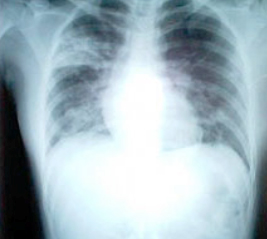

其他輔助檢查:SARS影像學檢查絕大部分患者在起病早期即有胸部X線檢查異常,多呈斑片狀或網狀改變。起病初期常呈單灶病變,短期內病灶迅速增多,常累及雙肺或單肺多葉。部分患者進展迅速,呈大片狀陰影。雙肺周邊區域累及較為常見,而胸腔積液、空洞形成以及肺門淋巴結增大等表現則較少見。對於胸片無病變而臨床又懷疑為本病的患者,1~2天內要複查胸部X線檢查。胸部CT檢查以玻璃樣改變最多見。肺部陰影吸收、消散較慢;陰影改變與臨床症狀體徵有時可不一致。